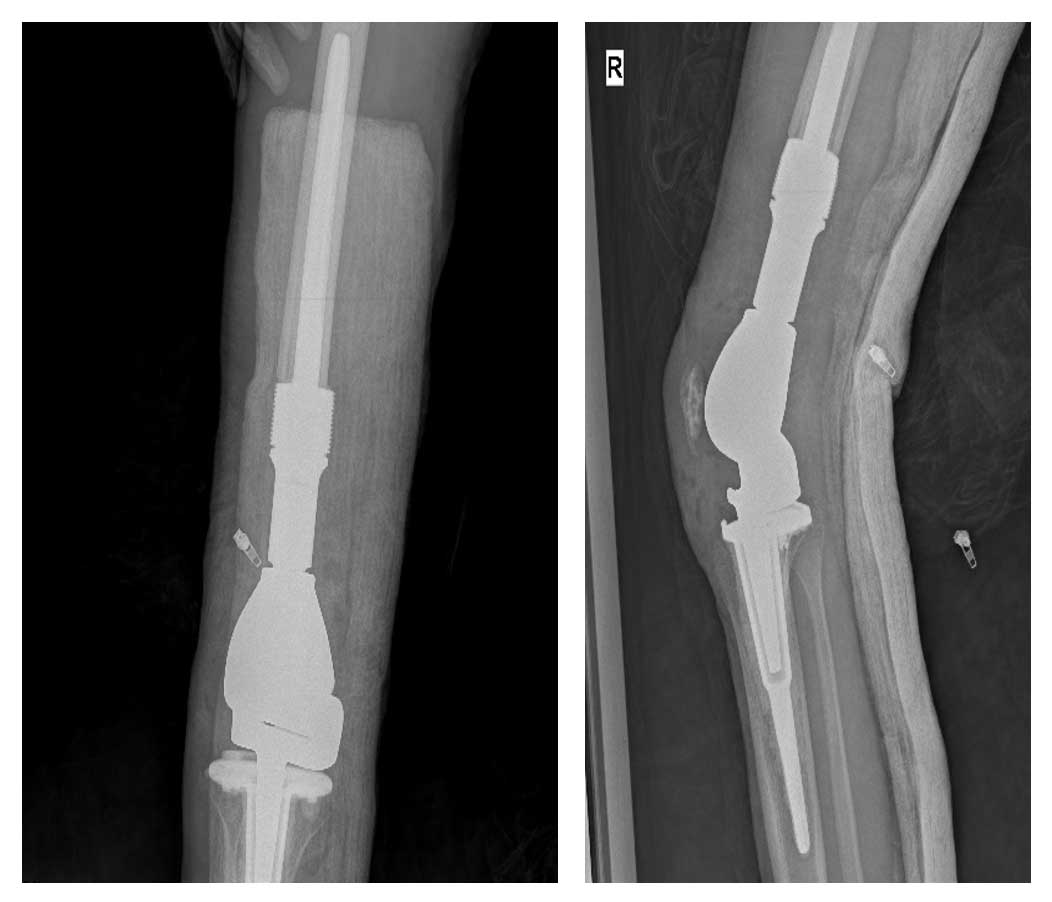

Hastaya kemoterapi sürecinin ardından ekstraartiküler diz rezeksiyonu uygulanmış ve tümörlü kemik çıkarılmıştır. Eksize edilen alan, distal femur tümör protezi ile yeniden yapılandırılmıştır. Böylece hem tümörün tamamen çıkarılması hem de diz fonksiyonlarının korunması sağlanmıştır.

Ameliyat Sonrası: Röntgende rezeksiyon sonrası uygulanan distal femur tümör protezi görülmekte.